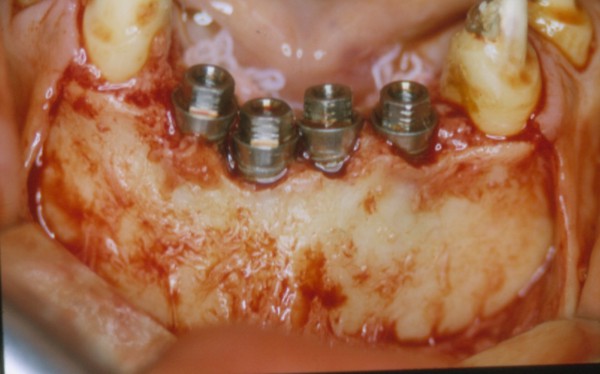

( REF.2) , abordamos la implantación inmediata, en lo que consideramos condiciones óptimas para la misma.